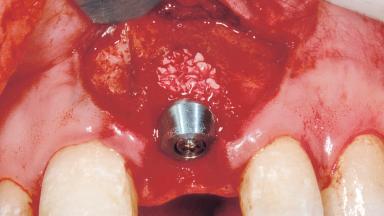

Immediate Placement of an Implant in a Maxillary Left Central Incisor Site

A 33-year-old female patient presented with an upper left central incisor that required extraction after a failed endodontic therapy. The tooth had been traumatized when the patient was a teenager and had undergone several endodontic treatments, including two apicectomy procedures. The patient was in good health and did not smoke. Clinical examination showed that the patient had a high lip line. In full smile, the gingival margins of the upper teeth were visible to the first molars. The gingival margins of central incisors 11 and 21 were only just showing. Examination of tooth 21 confirmed that the tooth was mobile and had hypererupted by 1 mm.

Placement Protocol | Immediate implant placement |

Socket Morphology | Single-root socket |

Socket Integrity | Damage to one or more bone walls |

Bone Volume | Damage to one or more socket walls |